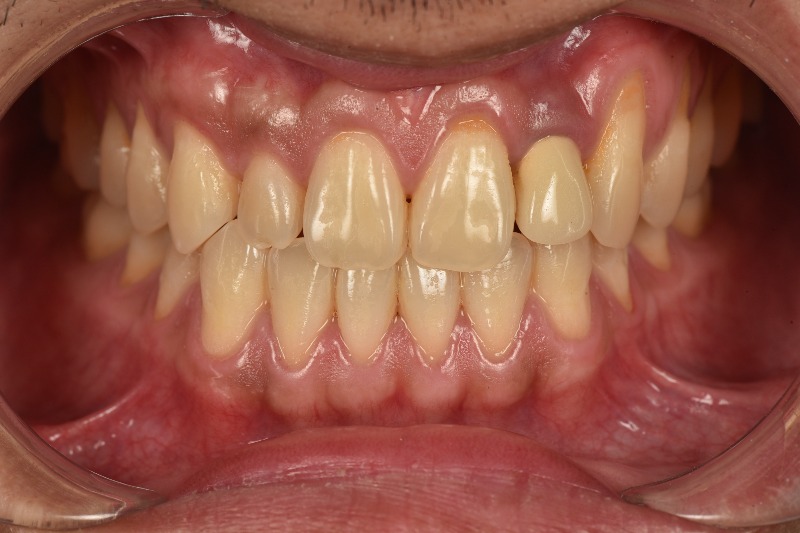

Tụt nướu răng ảnh hưởng thẩm mỹ trong trường hợp bệnh nhân cười lộ nướu (đường cười cao)

Một trong những yếu tố đáng quan tâm khi gặp tình trạng tụt nướu là sự ảnh hưởng đến thẩm mỹ của răng. Khi nướu bị tụt, chân răng lộ ra nhiều hơn, làm cho răng trở nên dài hơn. Điều này khiến cho nụ cười kém hài hòa và có thể tạo cảm giác không tự nhiên, thiếu sức sống.

Không chỉ vậy, màu sắc của chân răng cũng thường tối hơn và không có lớp men sáng bóng như phần thân răng. Đối với những người có răng cửa bị tụt nướu, tác động đến thẩm mỹ sẽ thấy rõ nhất, gây mất tự tin khi giao tiếp, cười nói.

Ngoài ra, tụt nướu còn khiến cho cấu trúc hàm mặt không cân đối, làm giảm đi sự cân đối và làm gương mặt có xu hướng lão hóa sớm. Đặc biệt, đối với những người chú trọng đến thẩm mỹ hàm răng, việc tụt nướu có thể trở thành một vấn đề gây ám ảnh.